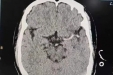

六旬大叔突发脑梗,专家紧急取栓救回一命!气温寒冷,医生重要提醒→

粤西首例!茂医神经内科介入团队为脑梗患者带来新疗法